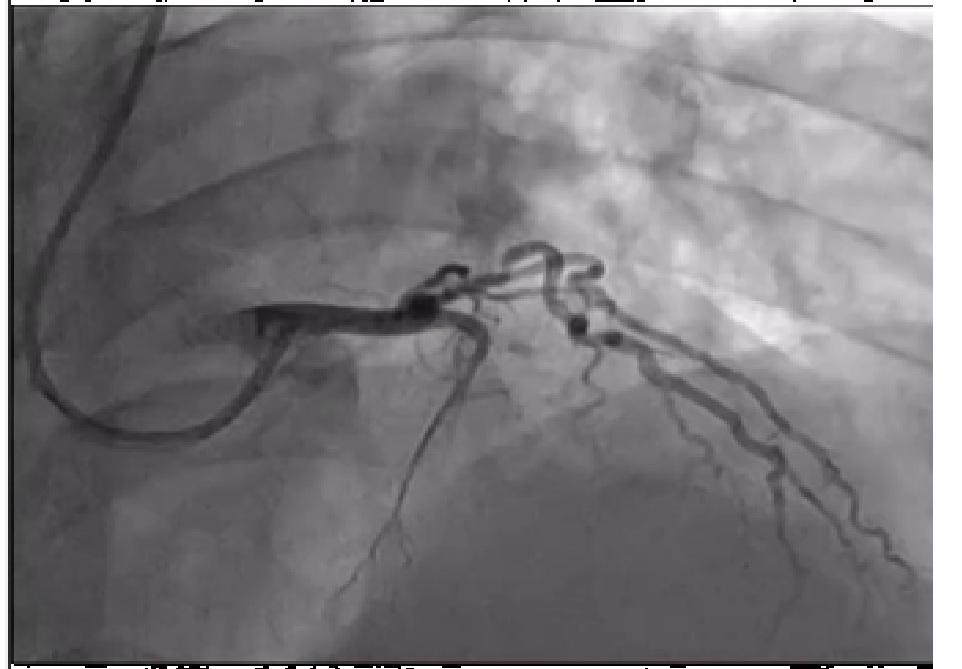

Coronary angiography has been performed, right coronary artery couldn't be find in the right coronary ostium, with EBU 3.5 right coronary artery was visualized arising from the left coronary ostium. LAD was occluded and RCA was with 99% stenosis in mid segment.

MOVIE-0008.mp4

Diagnostic angiography has been performed and occluded Left Anterior descending artery was visualized but, the right coronary artery couldn't be find from the right coronary ostium. 6F EBU 3.5 catheter trough the right radial approach has been inserted and we could visualize right coronary artery arising from the left coronary ostia. Direct stenting was performed with 3.5/38mm DES at 17 atm. After this procedure we continued to LAD, passed the occlusion with BMW wire after which predilatation with 2.5/20 mmx 14 atm has been performed and after that 3.0/28mm DES at 15atm was implanted with good end result